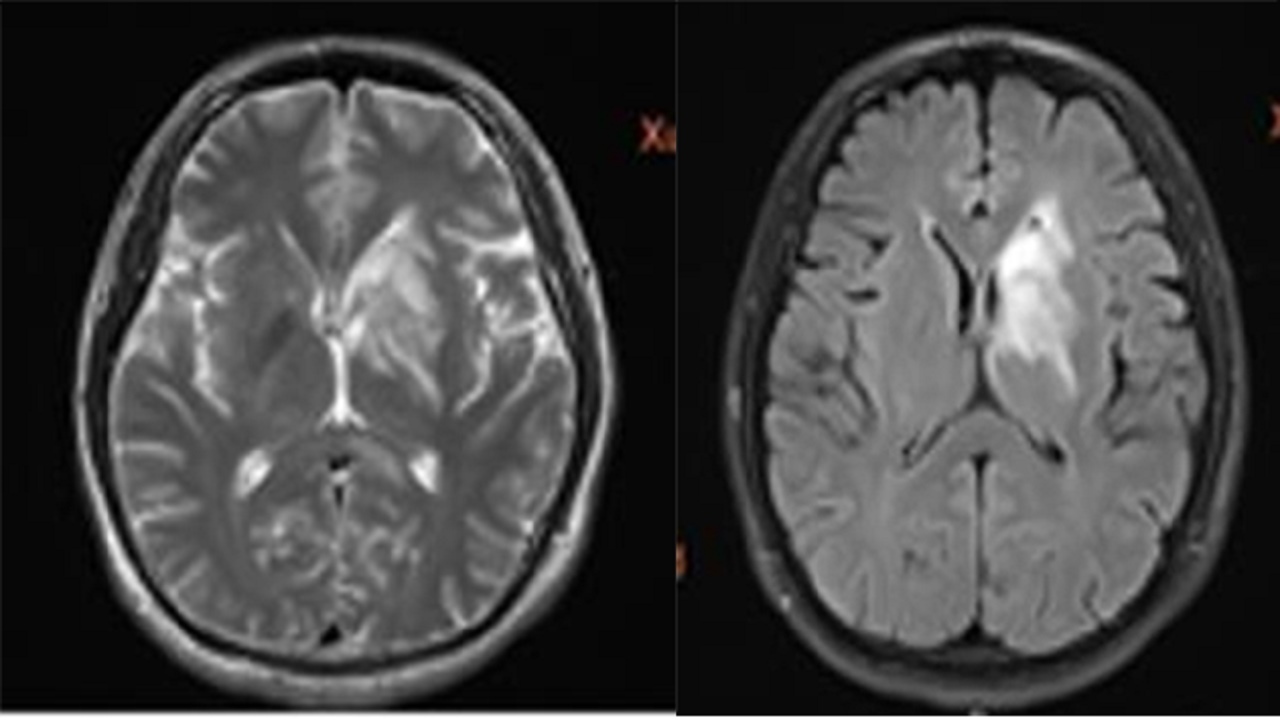

给予大剂量激素冲击治疗为主,患者症状明显改善,一月后复查头颅MR:

PRE